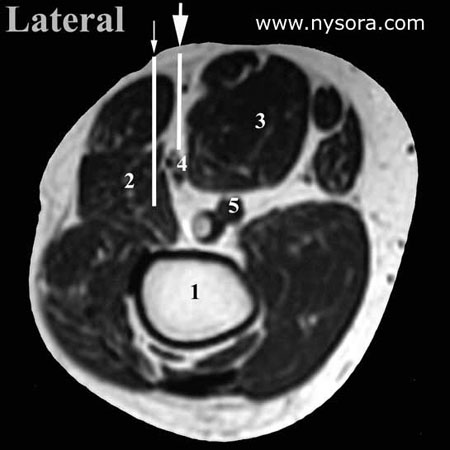

Figure 2. Simulation of the popliteal block using MRI images. The large arrow indicates a typical needle path in the intertendinous approach, whereas the small arrow shows too lateral insertion of the needle is common in the classical (triangle) approach. Data are expressed as means +/- standard errors for continuous measures. Since both approaches were studied in the same volunteers, McNemar chi-square tests were used to evaluate differences between the two approaches for the proportions presented in Table 2. Statistical analyses were performed using the Statistical Package for the Social Sciences (SPSS for Windows, version 5.0.2, Chicago, IL); p

Results The mean age, weight and height of the ten volunteers was 39 +/- 8 years (range 20-60 years), 78 kg +/- 12 kg (range 53-90 kg) and 174 cm +/- 9 cm (range 162-186 cm), respectively. The anatomical measurements of significance to popliteal block are presented in Table 1. The tibial and common peroneal components of the sciatic nerve appeared to be undivided or very close on MRI images at 7 cm above the popliteal fossa crease in all studied extremities. The proportion of simulated needle-to-nerve contacts, as well as other simulated needle insertion characteristics, are presented in Table 2. Simulated needle-to-nerve contact occurred significantly more often with the intertendinous (70%) than with the classical approach (25%). In the remaining 30% of needle simulations which did not contact the sciatic nerve using the intertendinous approach, 10-15° lateral redirection of the simulated needle placed the needle in line with the sciatic nerve, avoiding the risk of intersecting the popliteal artery or vein. In contrast, 75% of needle simulations using the classical approach missed the sciatic nerve and required medial redirection of the needle in order to reach the sciatic nerve. The required medial redirection of the needle (between 10° and 30°) in order to reach the sciatic nerve using the classical approach, carries a risk of intersecting the popliteal artery and vein which are situated medially to the sciatic nerve. Indeed, in three simulations through the classical approach the simulated needle path encountered the popliteal vessels with medial redirections of the needle. Furthermore, passage of the simulated needle through the biceps femoris muscle occurred less often with the intertendinous approach (5%) than with the classical approach (85%), Table 2. Discussion These data suggest that the intertendinous approach to popliteal block provides more accurate localization of the sciatic nerve in the popliteal fossa. Indeed, simulation of needle placement using the intertendinous approach resulted in needle-sciatic nerve contacts almost three times greater than with the classical technique. Furthermore, medial redirection of the needle (toward the popliteal vessels) was required to contact the sciatic nerve using the classical approach as opposed to the lateral redirection with the intertendinous technique. We speculate that the main reason for difficulty in localizing the sciatic nerve using the classical approach is an inability to accurately identify the boundaries of the popliteal fossa triangle. The base of the triangle is formed by the popliteal fossa crease and the sides by the semitendinosus and semimembranosus muscles medially and the biceps femoris muscle laterally. Whereas the muscular boundaries of the triangle are easily identified in cadavers, they are much more obscure and can be difficult to discern in patients (Figure 1). Consequently, often it is not clear what part of the muscles, tendon or body is palpated in many subjects. In contrast, the tendons of these muscles, which we proposed as landmarks for the intertendinous approach, are easily and accurately identified even in the obese patient (5). Importantly, these tendons do not converge into a triangle (as the muscles do higher in the thigh), but rather follow a near-parallel course in the popliteal fossa. These data and data from our recent clinical study (5) indicate that sciatic nerve is more accurately identified with the intertendinous approach using the tendons as landmarks rather than popliteal fossa triangle as is used in the classical approach to popliteal block. Since the muscle boundaries of the popliteal triangle are often difficult to appreciate with accuracy, it is possible that the tendons are often mistaken as the boundaries of the muscles. In that case, placement of the needle would then be too lateral for needle contact with the sciatic nerve. This medial redirection of the needle which would be required in order to reach the sciatic nerve may carry a higher risk of puncturing the popliteal vessels, especially when longer needles (e.g., 40 mm or longer) are used. In addition, needles inserted using the classical approach more often transect the body of the biceps femoris muscle, which may result in discomfort during the procedure. The use of MRI to compare needle trajectory does not provide information on clinical success of the block, or the difference in the ease of nerve localization between the intertendinous versus classical approaches. Nevertheless, in an earlier clinical study, we demonstrated that the intertendinous approach to popliteal block resulted in a 100% success rate (5). The results of the current study may also have been affected by bias due to the fact that unblinded investigators (two authors of the study) identified the landmarks for both approaches. However, the risk for this bias is small for two reasons. The landmarks for both the intertendinous and classical approaches were identified using “predetermined” criteria and there was uniform agreement between the two investigators with respect to the needle insertion site. Secondly, our finding of high frequency of needle to nerve contact with the intertendinous approach in the current study is in agreement with our earlier clinical study. In summary, under the conditions of our study, the intertendinous approach to popliteal block results in more proximate needle placement to the sciatic nerve in the popliteal fossa. In contrast, relying on the popliteal fossa triangle in the classical approach may result in needle placement which is too lateral to the sciatic nerve. This may require more attempts at nerve localization and redirection of the needle medially which places the popliteal vessels at risk of puncture. REFERENCES: 1. Vloka JD, Hadzic A, Mulcare R, et al. Combined blocks of the sciatic nerve at the popliteal fossa and posterior cutaneous nerve of the thigh for short saphenous vein stripping in outpatients: An alternative to spinal anesthesia. J Clin Anesth 1997;9:618-22. 2. Hadzic A, Vloka JD, Kuroda MM et al. The practice of peripheral nerve blocks in the United States. A national survey. Reg Anesth Pain Med 1998:23:241-6. 3. Rorie DK, Byer DE, Nelson DO, et al. Assessment of block of the sciatic nerve in the popliteal fossa. Anesth Analg, 1980; 59:371-6. 4. Brown DL: Popliteal nerve block. In: Brown DL, ed. Atlas of Regional Anesthesia. Philadelphia: W.B.Saunders Co., 1992:109-13. 5. Hadzic A, Vloka JD. A comparison of the posterior versus lateral approaches to the block of the sciatic nerve in the popliteal fossa. Anesthesiology 1998; 88:1480-6. |